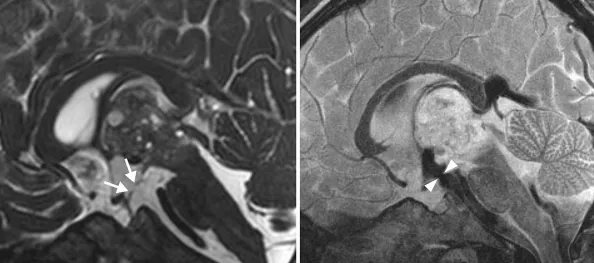

最终,KK再次被转诊至INC施罗德教授所在医院,教授为KK实行了开颅手术。毛骨悚然的是,等到看清怪瘤的真面目,众人都倒吸了一口凉气:“我们在他的肿瘤中发现了头发和牙齿样的物质,这提示我们这是畸胎瘤。”

术后,影像证实肿瘤被完全清除,KK恢复良好,无任何神经功能损伤。令人振奋的是,7年后的随访显示他健康如常,无复发迹象,脑积水也完全消失。这位5岁的小男孩再一次拥有了平安的人生。